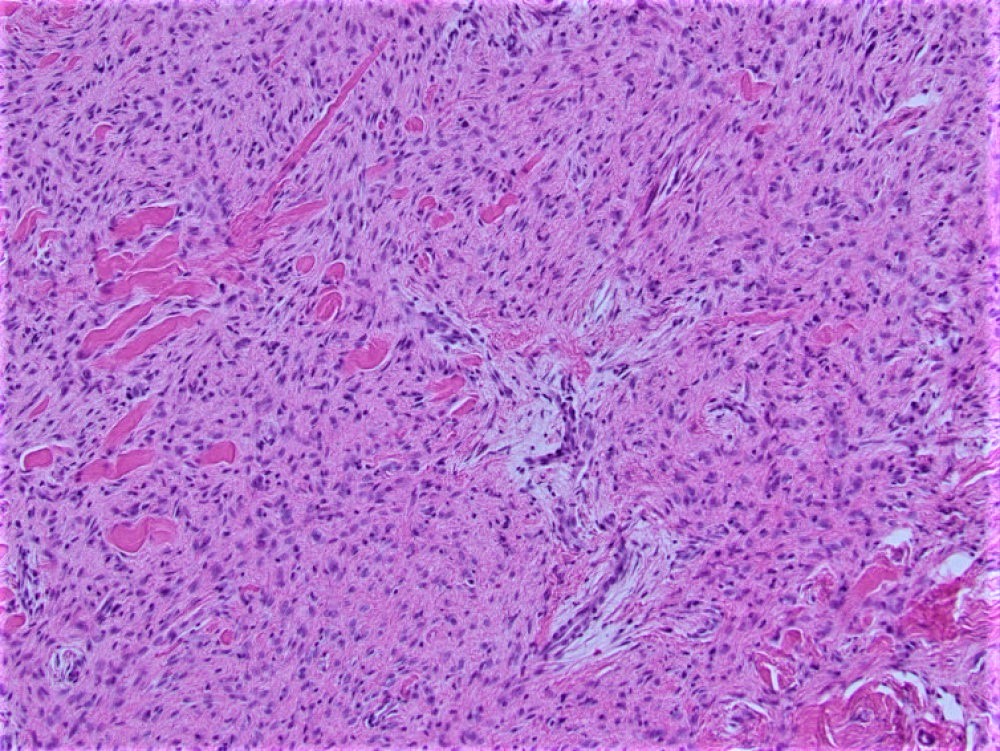

Sections of the biopsy revealed a proliferation of bland spindle cells arranged primarily in broad sweeping fascicles embedded in a dense collagenous stroma (Figure 2-3). There was no cytologic atypia and no mitoses were seen. Immunohistochemical staining demonstrated that the neoplastic cells were negative for SMA (Figure 4), desmin, CD34 (Figure 5), S-100 protein, and nuclear expression of β-catenin (Figure 6).